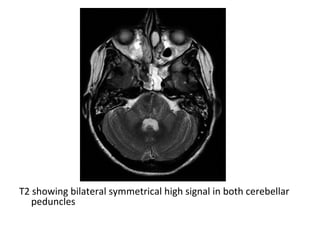

T2 showing bilateral symmetrical high signal in both cerebellar

peduncles

Axial T2 (A) shows symmetrical hyperintense signal in both the MCPs

(arrow) , Few hyperintense foci are also seen in pons , Diffusion (B) shows

hyperintense signal in both MCPs and in right paramedian pons ,

Corresponding ADC map (C) reveals reduced signal suggestive of restricted

diffusion